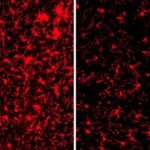

“Un composto chiamato BTSA1 (che sta per BAX Trigger Site Activator 1) è risultato essere l’attivatore più potente di BAX, provocando una rapida e ampia apoptosi quando è stato aggiunto a diverse linee cellulari umane di leucemia mieloide acuta”, afferma l’autore principale Denis Reyna, del laboratorio del Dr. Gavathiotis. I ricercatori hanno successivamente testato BTSA1 nei campioni di sangue da pazienti ad alto rischio di LMA. Sorprendentemente, BTSA1 ha indotto l’apoptosi nelle cellule dei pazienti LMA, ma non ha influenzato le cellule staminali destinate alla produzione di sangue.

Infine, i ricercatori hanno generato modelli animali di leucemia mieloide acuta innestando cellule umane di leucemia nei topi. BTSA1 è stata somministrata ad una metà dei topi con leucemia mentre l’altra metà è stata utilizzata come controllo. In media, i topi trattati con BTSA1 sono sopravvissuti 55 giorni rispetto ai topi di controllo (40 giorni), con il 43% dei topi trattati con BTSA1 vivi dopo 60 giorni e senza segni di LMA.

Importante, i topi trattati con BTSA1 non mostravano alcuna tossicità. “BTSA1 attiva BAX e provoca apoptosi nelle cellule LMA pur risparmiando cellule e tessuti sani, probabilmente perché le cellule tumorali sono preparate all’ apoptosi”, dice il Dr. Gavathiotis. Lo studio ha scoperto anche che le cellule LMA da pazienti contenevano livelli di BAX significativamente più elevati rispetto alle normali cellule del sangue da persone sane.